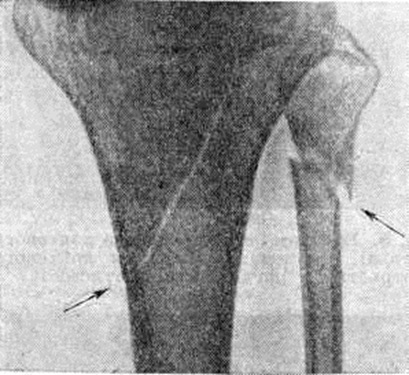

Основной рентгенологическое признак нарушения целости кости — линия Переломы Большое диагностическое значение имеет смещение отломков, наличие которого настолько бесспорно доказывает нарушение целости кости, что надобность в дифференциальной диагностике отпадает. Как бы подробно ни была описана рентгенологическое картина Переломы, наиболее полное и правильное представление о степени и характере смещения отломков врач может составить лишь при непосредственном просмотре снимков. Захождение отломков одного за другим при продольном смещении на рентгенограмме в одной проекции может сопровождаться наслоением теней концов отломков — так называемый суперпозицией теней. В этом случае точное определение смещения отломка возможно на основании данных снимков во второй проекции. При Переломы плоских костей (лопатка, ребра, таз и другие), при которых по техническим причинам производство снимка во второй проекции затруднено, суперпозиция отломков часто является единственным достоверным признаком Переломы Распознавание продольных смещений с расхождением отломков обычно не представляет каких либо затруднений. Подобного рода смещения наблюдаются при Переломы надколенника с разрывом связочного аппарата, локтевого отростка, вертелов бедра, отрывах костных выступов, к которым прикрепляются мышцы, сокращающиеся при повреждениях и приводящие к расхождению. Интерпозиция мягких тканей между отломками костей при рентгенологическое исследовании не распознается. Различные виды Переломы в наиболее информативных проекциях представлены на рисунок 4—11.

Рис. 10.

Прямая рентгенограмма верхней трети голени: косая трещина проксимального метаэпифиза большеберцовой кости и перелом малоберцовой кости (указаны стрелками).